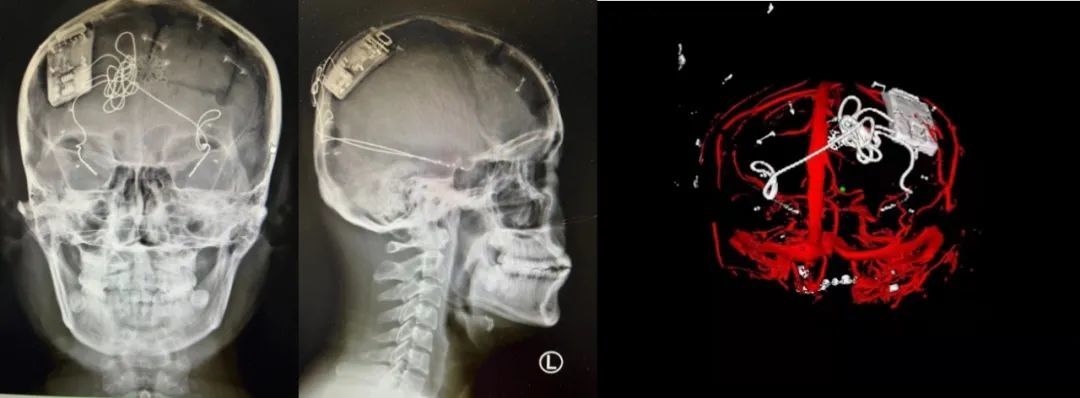

本次手術(shù)過程順利,術(shù)中刺激器各項(xiàng)指標(biāo)均工作正常,術(shù)后重建顯示電極位置精準(zhǔn),腦電信號(hào)清晰?;颊邽槟行裕朐汉笤\斷為雙側(cè)顳葉癲癇,此類癲癇為開顱手術(shù)的相對(duì)禁忌癥,在藥物無法控制的情況下,傳統(tǒng)治療效果欠佳 。

術(shù)前經(jīng)過宣武醫(yī)院癲癇多學(xué)科專家團(tuán)隊(duì)詳細(xì)的臨床評(píng)估,包括視頻腦電監(jiān)測(cè)、頭顱磁共振及三維 CT 掃描、腦核醫(yī)學(xué)檢查等,全面評(píng)估了患者病情及致癇灶定位情況。

由于患者臨床診斷為雙側(cè)顳葉癲癇伴海馬硬化,無法通過致癇灶切除等傳統(tǒng)外科手術(shù)方式獲益,決定進(jìn)行閉環(huán)反應(yīng)性神經(jīng)刺激系統(tǒng)植入手術(shù)治療。并根據(jù)閉環(huán)神經(jīng)刺激技術(shù)特點(diǎn),為患者“量身定制”植入方案,尤其是電極植入位點(diǎn)和脈沖發(fā)生器固定部位等,為手術(shù)的順利實(shí)施奠定了良好基礎(chǔ)。

團(tuán)隊(duì)根據(jù)術(shù)前計(jì)劃,在手術(shù)機(jī)器人輔助下完成雙海馬長軸電極及 IPG 植入,術(shù)后重建顯示電極位置精準(zhǔn),腦電信號(hào)清晰。術(shù)后第二天,患者即下床活動(dòng),身體狀況恢復(fù)良好。